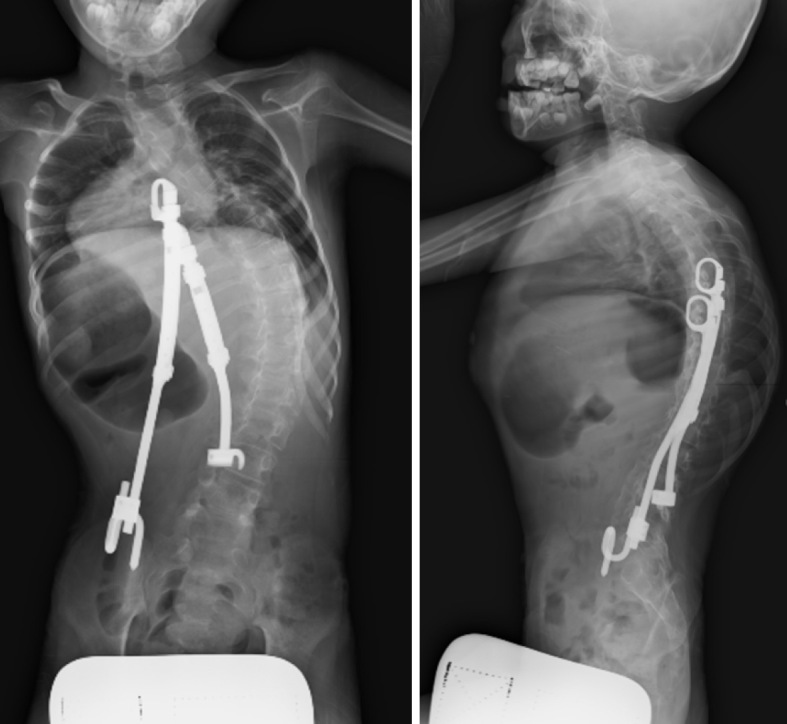

A Case of Early Onset Scoliosis with Trisomy 1q and Monosomy 21q.

Abstract Image